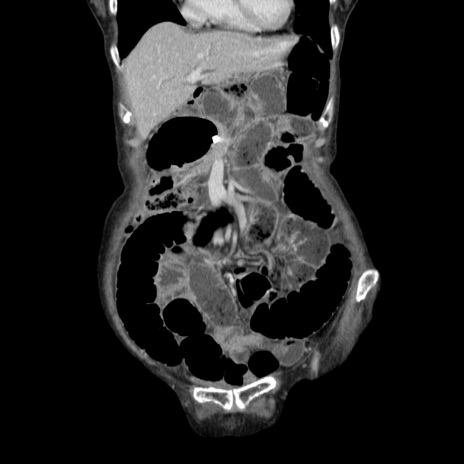

症例25(冠状断像)

【症例】80歳代女性

【主訴】胸のつかえ感

【現病歴】約9時間前に食後から胸のつかえた感じあり、嘔吐あり、来院。

【既往歴】胃癌(全摘)、胆摘、虫垂炎

【身体所見】心窩部に圧痛あり、反跳痛なし。

【データ】WBC 5700、CRP 0.05